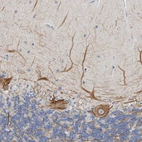

Immunohistochemistry analysis in human cerebral cortex and endometrium tissues using HPA023138 antibody. Corresponding NEFM RNA-seq data are presented for the same tissues.